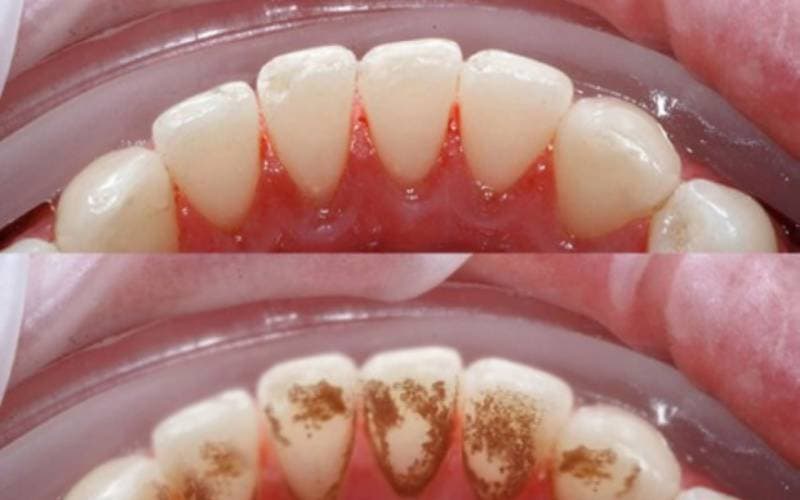

1.3. Tác hại của cao răng

Nhiều vấn đề và biến chứng được ghi nhận từ tình trạng cao răng:

– Viêm nướu: Cao răng là nguyên nhân chính gây viêm nướu, biểu hiện bằng các triệu chứng như nướu sưng đỏ, chảy máu chân răng, hơi thở có mùi hôi. Viêm nướu điều trị mụôn, không đúng cách dễ tiến triển thành viêm nha chu, dẫn đến tổn thương các mô hỗ trợ xung quanh răng và có thể dẫn đến mất răng.

Cao răng gây nhiều khó chịu và tiềm ẩn nguy cơ mắc phải nhiều bệnh lý răng miệng